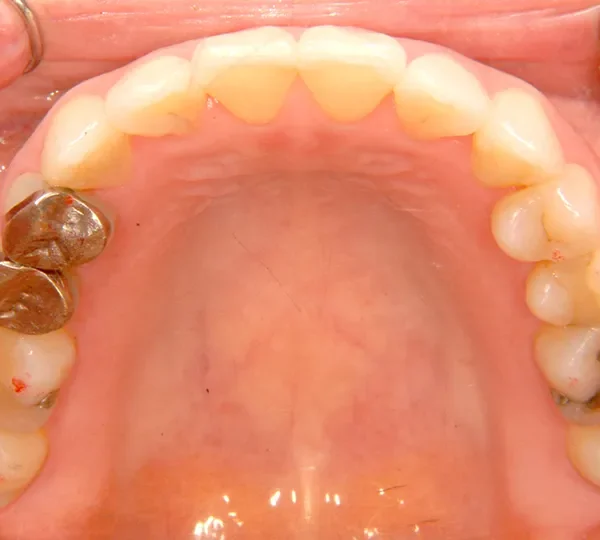

• 治療終了2年後

治療終了2年後

また今回の症例は、歯科矯正用アンカースクリューを用いた治療の本に掲載されました。